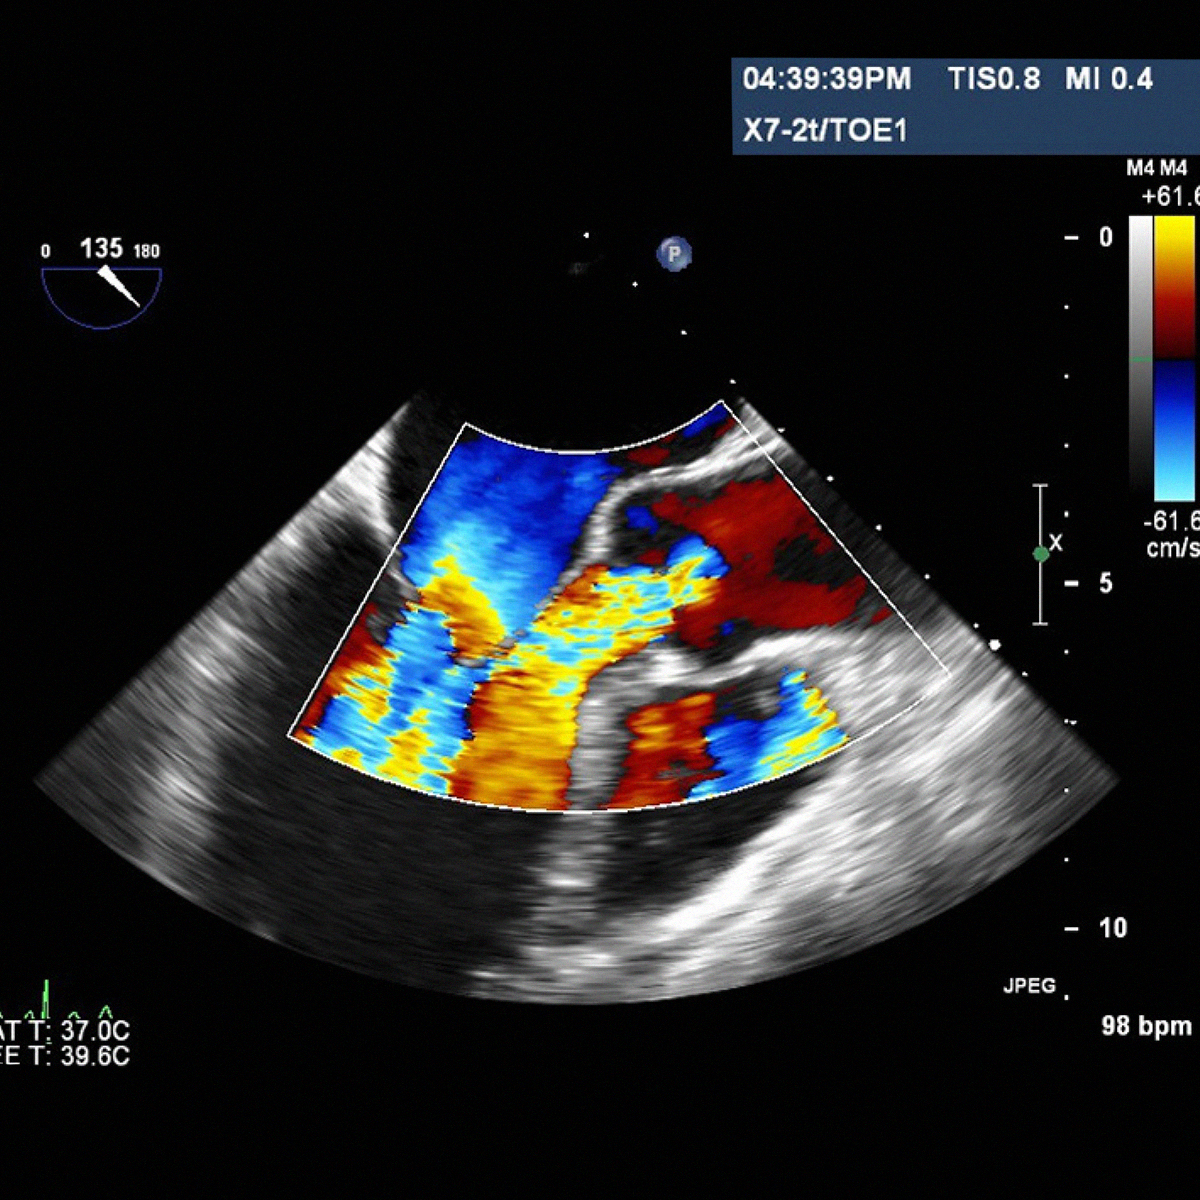

L' ecocardiografia è una metodica con cui si studiano il cuore e il flusso del sangue attraverso le valvole per mezzo degli ultrasuoni. A differenza delle radiazioni utilizzate in radiologia, gli ultrasuoni sono innocui, per cui non è necessaria alcuna precauzione e l'esame può essere eseguito su qualunque paziente innumerevoli volte.. Prima di analizzare la differenza tra Ecocolordoppler ed Ecocardiogramma dobbiamo premettere che entrambe sono tecniche della diagnostica per immagini che utilizzano gli ultrasuoni per indagare le strutture cardiache.. Ecocardiogramma. L'Ecocardiogramma è un esame che permette di visualizzare le immagini del cuore al fine di individuare possibili anomalie della struttura e della.

L'Ecocardiogramma, ecografia del cuore o ecocardiografia è un esame diagnostico che permette di ottenere immagini delle valvole cardiache (aortica, mitrale, tricuspide) e del cuore in generale, per valutare il grado di insufficienza cardiaca, cioè per misurare la forza di contrazione delle pareti del cuore, oppure per studiare i difetti cardiaci congeniti.. Qual è la principale differenza tra elettrocardiogramma (ECG) e ecocardiogramma? L'elettrocardiogramma ECG studia il segnale elettrico del cuore, mentre l'ecocardiogramma è un'ecografia che mostra quindi la morfologia del cuore. Permette di valutare le dimensioni dell'organo, lo stato del pericardio, la contrattilità e le performance.